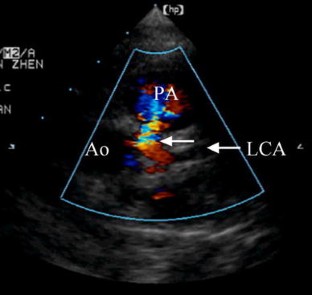

Fig. 4